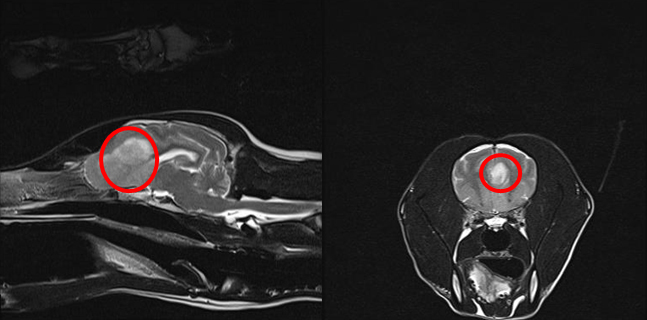

患者の頭部MRI撮影像(T2強調画像)

左図:矢状断面、右図:横断面

前頭洞にT2強調像で高信号な病変を認める